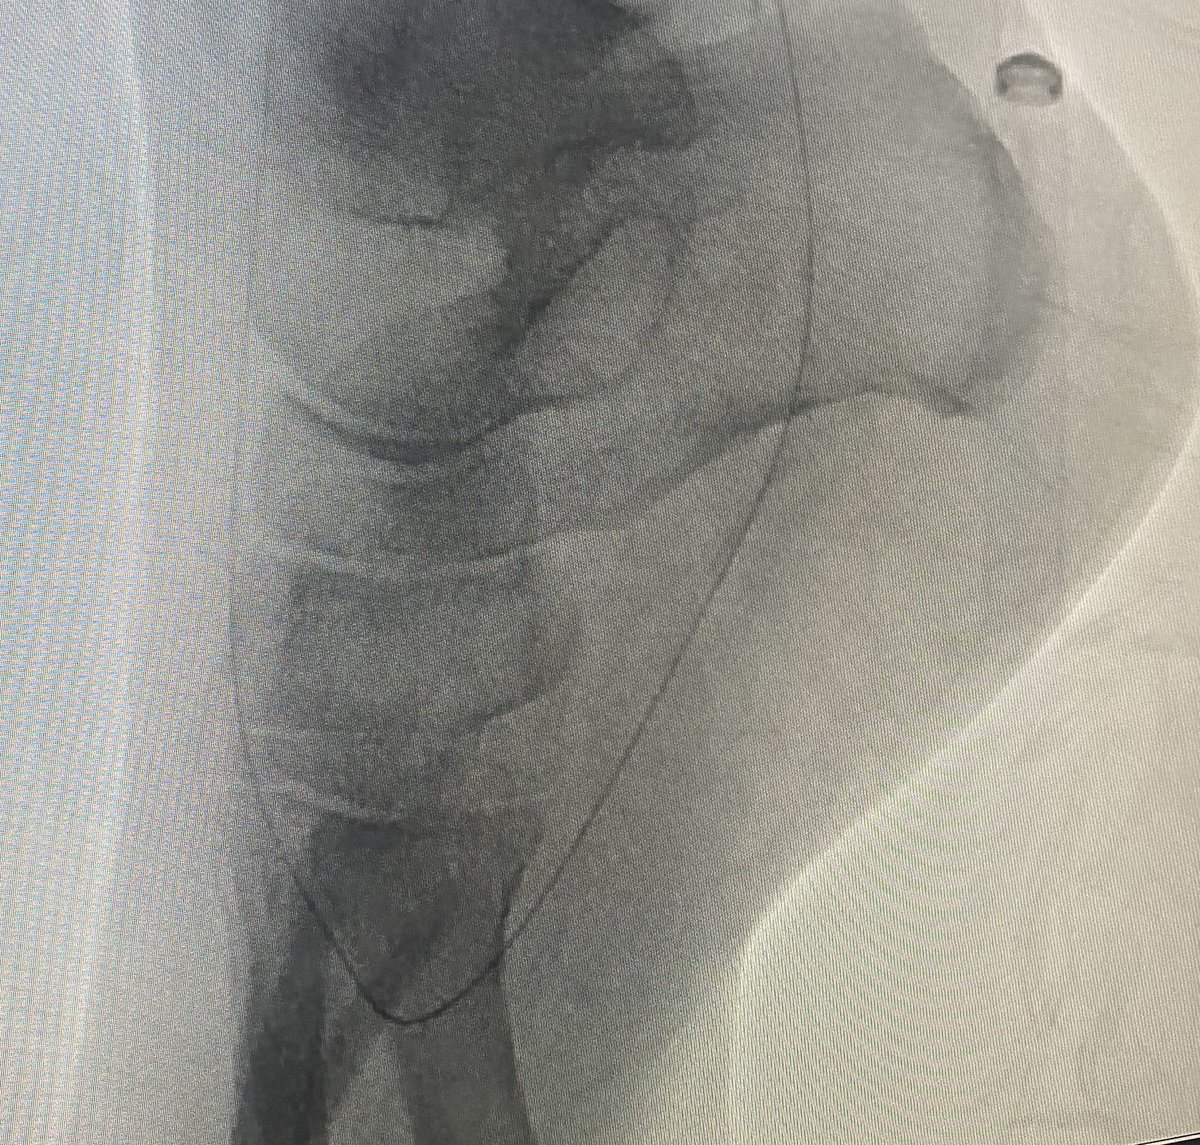

Our IR Section Chief @arzybule demonstrating his skills utilizing #nBCA to embolize a large shoulder AVM with our amazing #ESIR residents @Rubin129 #DannyReyes! Everybody loves a GlueEmbo case!!!